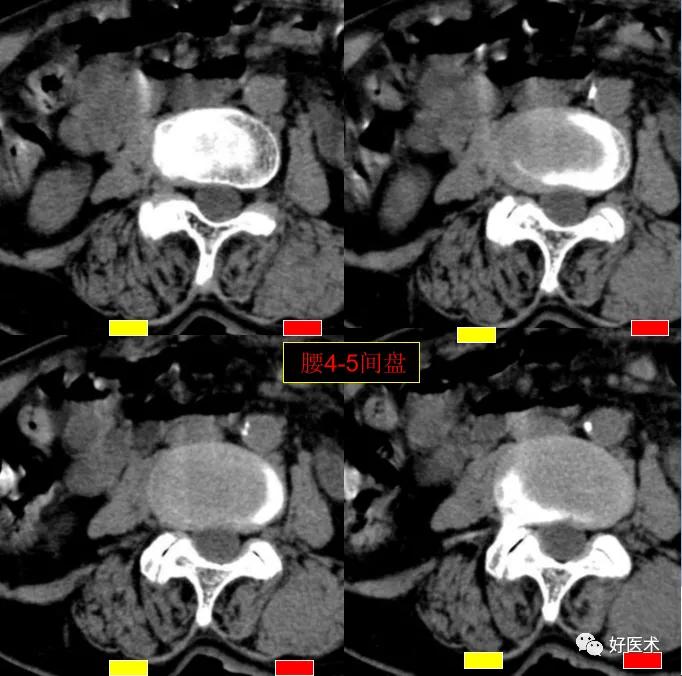

CT图像,腰椎常规采用序列扫描,腰椎体2层,腰间盘4层,层厚2.5mm,一般扫描范围包括腰2--骶1椎体及所属间盘。

腰4-5间盘膨隆, 双侧椎小关节积气

发现了什么?左侧竖脊肌较右侧明显肿胀饱满, 肌间脂肪间隙消失!!